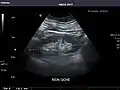

Right kidney

Kidneys: Right and left kidneys measure 11.5 cm and 12 cm in length respectively. No hydronephrosis. Small left lower pole kidney cyst.